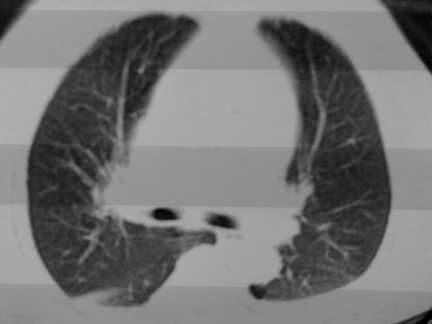

标题: CT13142:女 80 胸闷、气短、1w [打印本页]

标题: CT13142:女 80 胸闷、气短、1w

右肺炎性变

双侧胸腔积液

胸膜肥厚,

右肺感染;双侧胸腔少量积液,心影增大,可能与心功不全有关;胸内甲状腺肿。

胸内甲状腺肿;右肺感染;双侧胸腔少量积液。

胸内甲状腺肿;右肺中叶感染;双侧胸腔少量积液;心影增大,考虑有心功能不全。